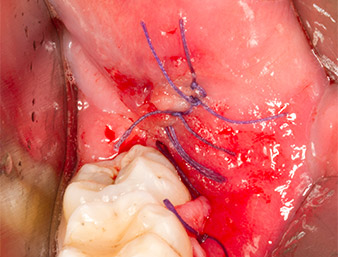

A continuación, el tejido óseo autógeno (figura 13) se incorporó en el alvéolo y en el defecto óseo circundante (figura 14). Un velo de colágeno sirvió de protección para el nervio expuesto y cubrió las virutas óseas hasta el nivel del hueso (figura 15). Se aplicaron puntos de sutura con hilos Vicryl de grosor 4.0, que cerraron los tejidos blandos abiertos (figura 16). Tras la operación, se prescribió un preparado de ibuprofeno (Seractil 400 mg 3x1) y un antibiótico con amoxicilina y ácido clavulánico (Augmentine 1g 2x1).